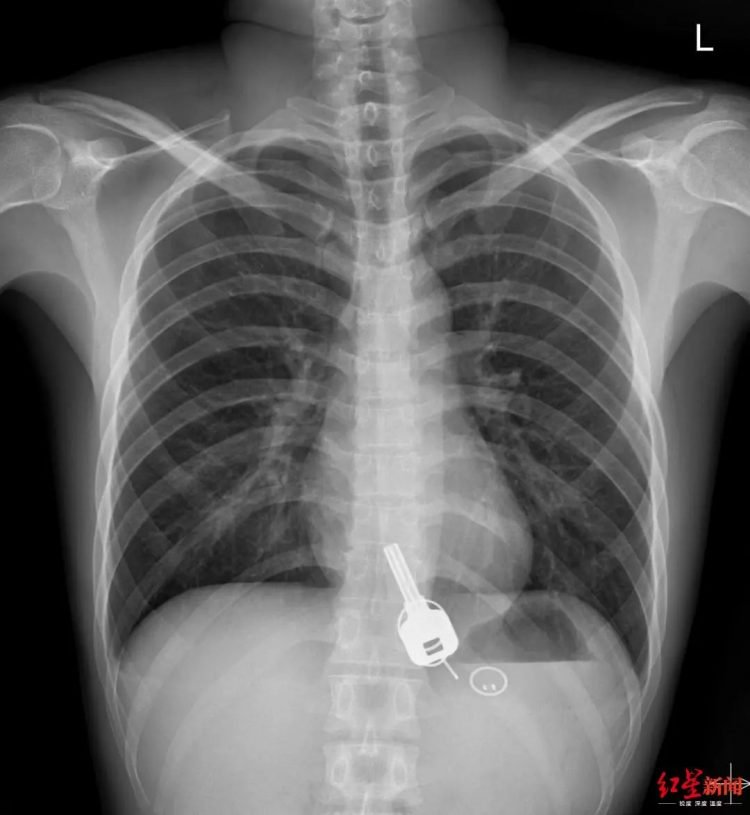

Ảnh chụp X-quang cho thấy chìa khóa nằm trong cơ thể Chang.

Kết quả chụp X-quang cho thấy có hình chìa khóa in rõ trong cơ thể Chang. Chang nói với các bác sĩ rằng đúng là mình bị mất chìa khóa, nhưng không hiểu vì sao nó lại nằm trong cơ thể.

Trang Sohu đưa tin, Chang đã rất sốc khi các bác sĩ cho anh ta xem ảnh chụp X-quang. Các bác sĩ nói chìa khóa quá lớn, xâm nhập qua đường tiêu hóa, nên để nó thải ra theo cách bình thường rất khó